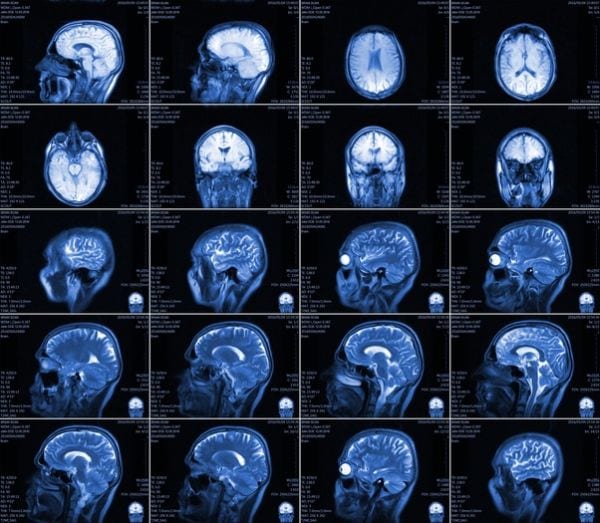

Tali affermazioni sono importanti perché rappresentano il punto di partenza di un’importante ricerca scientifica che ha portato alla scoperta del meccanismo che, appunto, fa partire le metastasi e le fa arrivare fino al cervello. Agli autori del lavoro – realizzato grazie ad una collaborazione tra il gruppo di ricerca neuro-oncologica del dipartimento di Neuroscienze dell’ospedale Molinette di Torino e il Cnr di Madrid – va il merito di aver individuato la presenza inaspettata di una proteina – definita Stat3 – sulla membrana delle cellule sane, nei cosiddetti astrociti reattivi, che circondano le metastasi cerebrali. Tale proteina si è rivelata pronostica, vale a dire che i pazienti nella quale viene riscontrata hanno purtroppo una sopravvivenza molto più breve rispetto agli altri.

Il valore della ricerca, pubblicata sulla prestigiosa rivista scientifica Nature Medicine, è quello di aprire la strada a nuove terapie farmacologiche, considerate oggi limitate e insoddisfacenti. Passare dalla teoria alla pratica a questo punto diventa estremamanete importante, ecco perché la prossima tappa sarà quella di verificare attraverso degli studi clinici la possibilità di bloccare con farmaci specifici la STAT3.